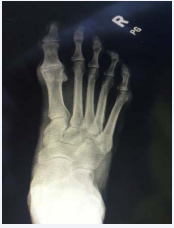

Before any treatments are offered a series of radiographs should be taken to assess the pathology of the first MPJ. This usually consists of the lateral, anteroposterior, and the medial oblique views of the affected foot. The AP view allows the practitioner to assess the joint space, while the lateral and MO views will show any associated spurring around the joint as well as the joint space. Occasionally loose bodies or sub chondral cysts are seen in any view taken. Sclerosis of the bone may also be seen on the radiographic studies since this is one of the ways that the bone tries to heal itself (Figure 1-4).

Figure 2: In this radiograph you can see the flattened appearance of the metatarsal head as well as significant joint space narrowing.